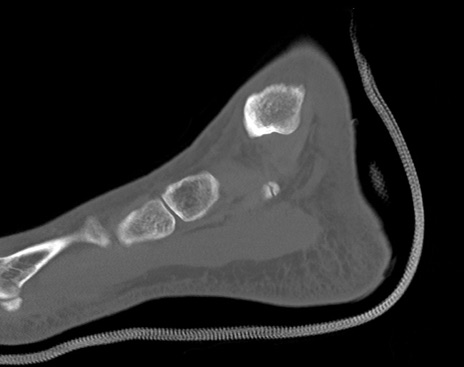

症例37 左足関節CT(矢状断像)

左足関節CT

横断像